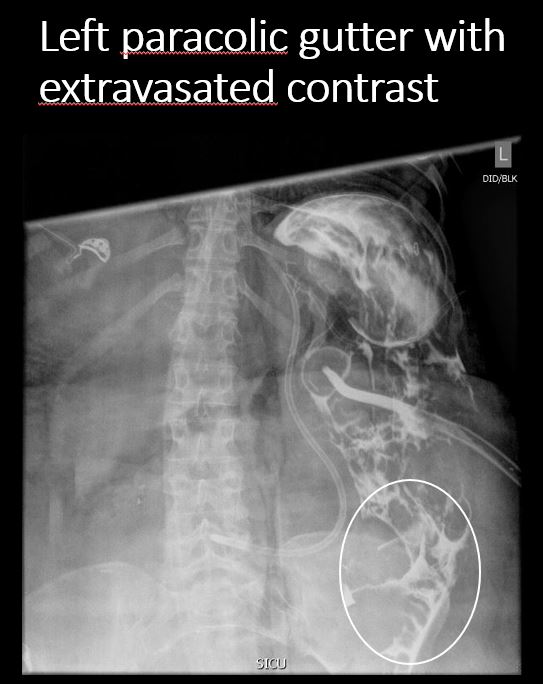

The paracolic gutters are abnormal. [Yes/No]